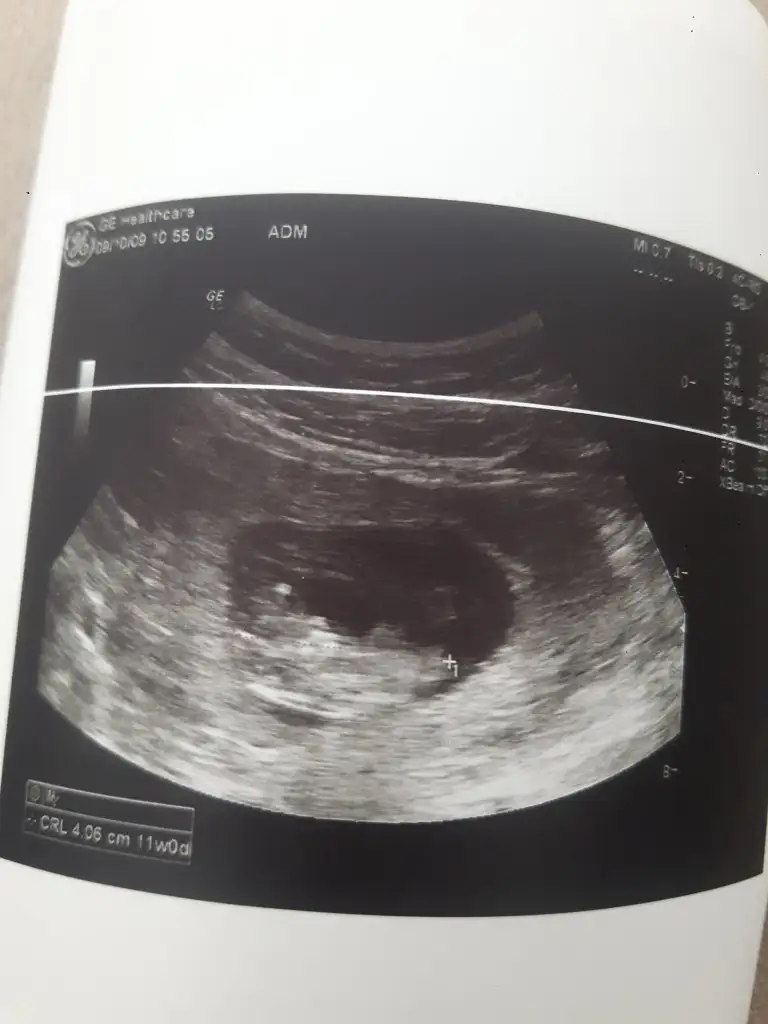

Gittim geldim cok sukur . Doktor cok guzl yerlesmis. Gayet ii dedi. Yine ayni devlt hastnesine gittim. Bu sefer hemen gorundu sipa cok sukur. Sjmdi yeni yeni idrak ediorm varligini desem yeridir. 😍 icim oyle rahatldi ki kizlr anlatamam. Tam bebek tipini almisti 😊Rabbimz sizlere de bi an once nasip etsin.

Eki Görüntüle 2543764

Masallahh yaa çok sevindim adına canm Rabbim sağlıkla devam ettirsin gebeliğini hayırlısıyla 🙏😍 Ultrason görüntüsünden çok anlamam ama bebek dediğinde boynum kıldan ince, Rabbimin mucizesi... Allah'ım bizlere nasip et bizlere de inşallah 🤲